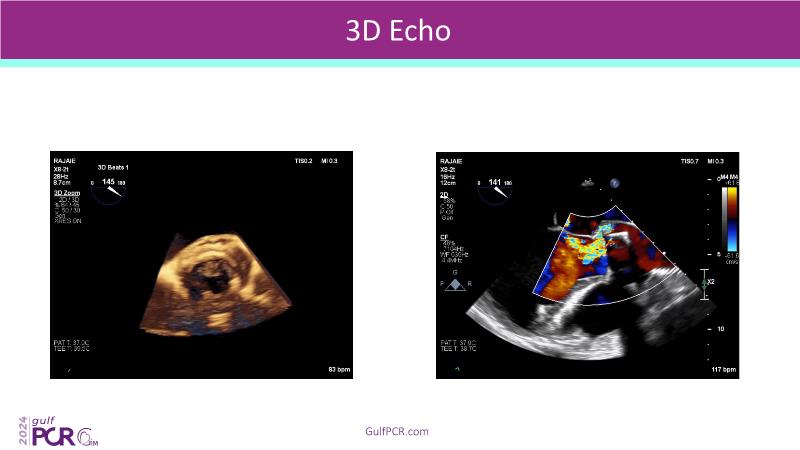

Stay ahead in TAVI innovation by exploring the advanced balloon-expandable Myval THV series. This session highlights the latest clinical data, optimal sizing and implantation techniques, and valuable real-world insights, including long-term follow-up results.

- To learn about the novel balloon expandable Myval THV series and the up-to-date clinical evidence for it

- To understand the best practices for Myval sizing and implantation technique for best outcomes

- To update on its experience and follow-up in "real-world" patient registries